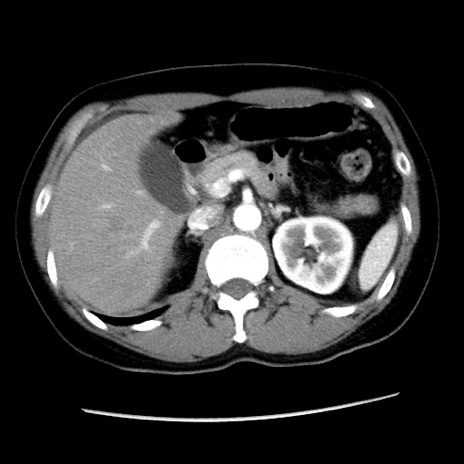

冠状断像

【症例】 50歳代女性

【主訴】 腹痛

【現病歴】前日生レバーを食べた。今朝に排便あり。 昼前に突然発症の腹痛を生じ、当院救急外来を受診した。

【既往歴】 子宮筋腫にてで子宮全摘後

【身体所見】 意識清明、腹部:平坦、軟、下腹部やや左を中心に圧痛・反跳痛あり、筋性防御あり

【データ】WBC 7800、CRP 0.07